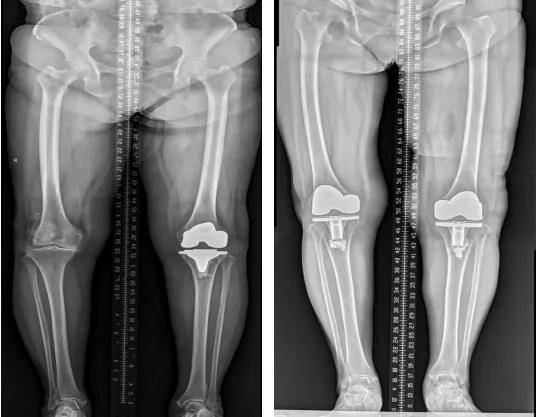

膝关节外科技术力量雄厚,科室配备医护人员30人,其中,主任医师5名,副主任医师3名,主治医师3名,住院医师4名,博士1名,硕士研究生4名。开放床位48张。该科擅长对膝关节严重创伤(包括股骨远端骨折、髌骨骨折、胫骨平台骨折等)、膝骨关节炎阶梯化治疗、保膝治疗、膝关节微创单髁置换术、全膝关节置换术、膝关节翻修术具有丰富的临床诊疗经验,追求微创、无痛、快速康复。对膝关节骨性关节炎采取阶梯化治疗方案,坚持中西并重、内外兼治的原则,取得满意的治疗效果。早期利用中医中药的传统优势,使用中医外治法,例如烫熨治疗、中药涂擦、雷火灸、中药塌渍等,同时辩证内服本院中药制剂及内服方药以及配合西药治疗,开展健康教育,运用运动疗法、物理治疗等辅助支持;中期开展软骨修复、截骨术、单髁置换术、髌股关节置换术等;对于终末期的膝关节OA采用全膝关节置换术。【膝关节外科主要特长】 (一)膝骨关节炎高位截骨术

(三)膝骨关节炎全膝关节置换术

(四)膝关节置换术后关节翻修术